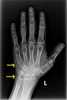

Brachydactyly

Localized brachydactyly

Short and broad distal phalanges of hand

Short broad distal phalanx of thumb

Short fourth metacarpal

Short metacarpal